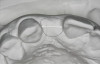

Figure 7  These images summarize the various dimensional assessments that underscore the Rules of Six guidelines, which enable simple planning for uncomplicated single-tooth dental implant therapy: Finding mesiodistal or inter-radicular (Fig 7), buccolingual (Fig 8), and inter-occlusal (Fig 9) distances of 6 mm can assure uncomplicated implant placement and restoration.

Figure 7

Figure 8  These images summarize the various dimensional assessments that underscore the Rules of Six guidelines, which enable simple planning for uncomplicated single-tooth dental implant therapy: Finding mesiodistal or inter-radicular (Fig 7), buccolingual (Fig 8), and inter-occlusal (Fig 9) distances of 6 mm can assure uncomplicated implant placement and restoration.

Figure 8

Figure 9: These images summarize the various dimensional assessments that underscore the Rules of Six guidelines, which enable simple planning for uncomplicated single-tooth dental implant therapy: Finding mesiodistal or inter-radicular (Fig 7), buccolingual (Fig 8), and inter-occlusal (Fig 9) distances of 6 mm can assure uncomplicated implant placement and restoration.

Figure 9